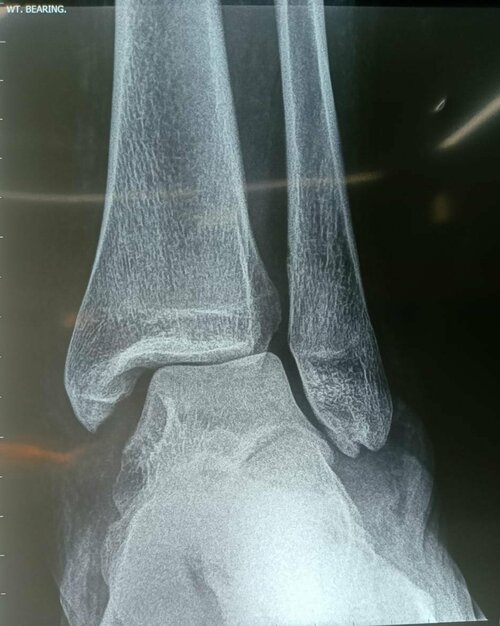

Foot ball injury causing complex syndesmosis ligament injury treated by unique technology | Dr. Girish Motwani

A 25 year old patient had a Football injury and the injury had the made patient unable to put weight also the patient had Tenderness on the deltoid &a...

Foot Ball Injury Treated by Complex Ankle Ligament - Syndesmosis | Dr. Girish Motwani

A 25 year old patient had Football Injury and the injury had the patient unable to put weight also the ppatienthad Tenderness on dthe eltoid & ATF...